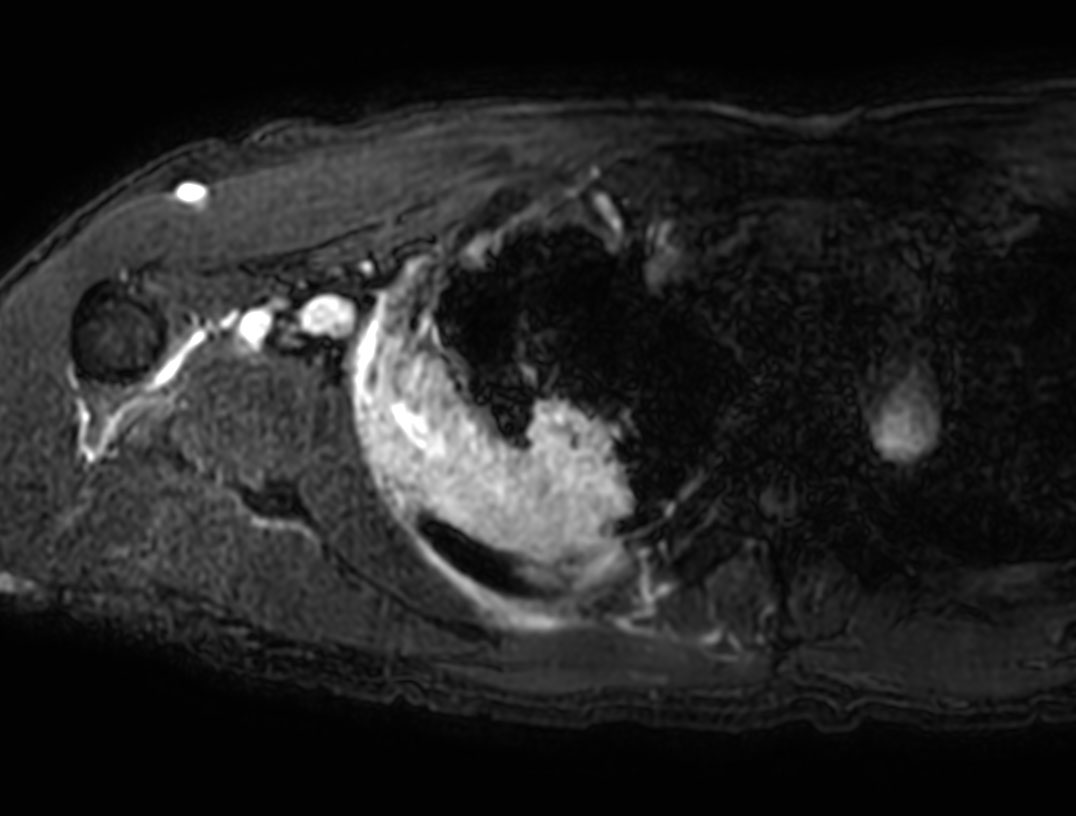

Axial DWI (b800)